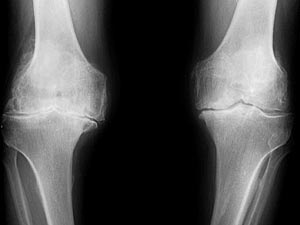

A 77-year-old male from New Jersey presented the Clinic with a complaint chiefly of right knee pain, stating pain occurs almost continually. Pain described as dull, worse when walking, and mostly located medially (inner knee area ). Pain has persisted for 30 years since an incident while patient walked downstairs at home when knee 'locked' at 90-degree angle. Prior to locking episode, patient was an avid sportsman and runner, never experiencing pain in either pursuit. At time that knee lock occurred, a physician unlocked knee by injection of anesthetic and application of traction to stretch joint. Following treatment, patient relates knee began to deform and became bowed. Arthroscopic surgery was undertaken at a later time to alleviate constant pain. Prior to this locking episode, he was avid sportsman and a runner and never experienced pain. His knees were straight. When his knees locked, he saw a local physician who after injecting his knee with anesthetic was able to unlock the knee by traction (medical lingo: the pulling of or tension established in one body part), he says ever since then his knee started to deform and bowing. After wards he had arthroscopy in the right knee which helped him with the pain. His past medical history of Atrial Fibrillation and takes Digoxin for it. Otherwise he is a good candidate for a total knee replacement. He also takes Celebrex which eases his pain. Locking of the knee is a common phenomenon, patients typically describe the knee is stuck in a particular position ,and not being able to move the knee. Most common cause of it is usually a meniscus tear. Other common causes are ACL Damage, loose bodies and patellar dislocation. Patients inability to fully extend the knee produces excruciating pain.